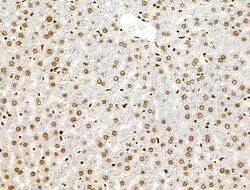

Invitrogen™ Phospho-AKT1 (Ser124) Polyclonal Antibody

Antibody detects endogenous levels of AKT1 only when phosphorylated at Ser124.

| Immunohistochemistry (Paraffin), Western Blot, Immunocytochemistry | |

| A synthesized peptide derived from human AKT1(Accession P31749), corresponding to amino acid residues around phosphorylated Ser124. | |

| Human, Mouse, Rat | |